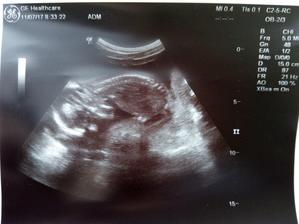

11.7.2017